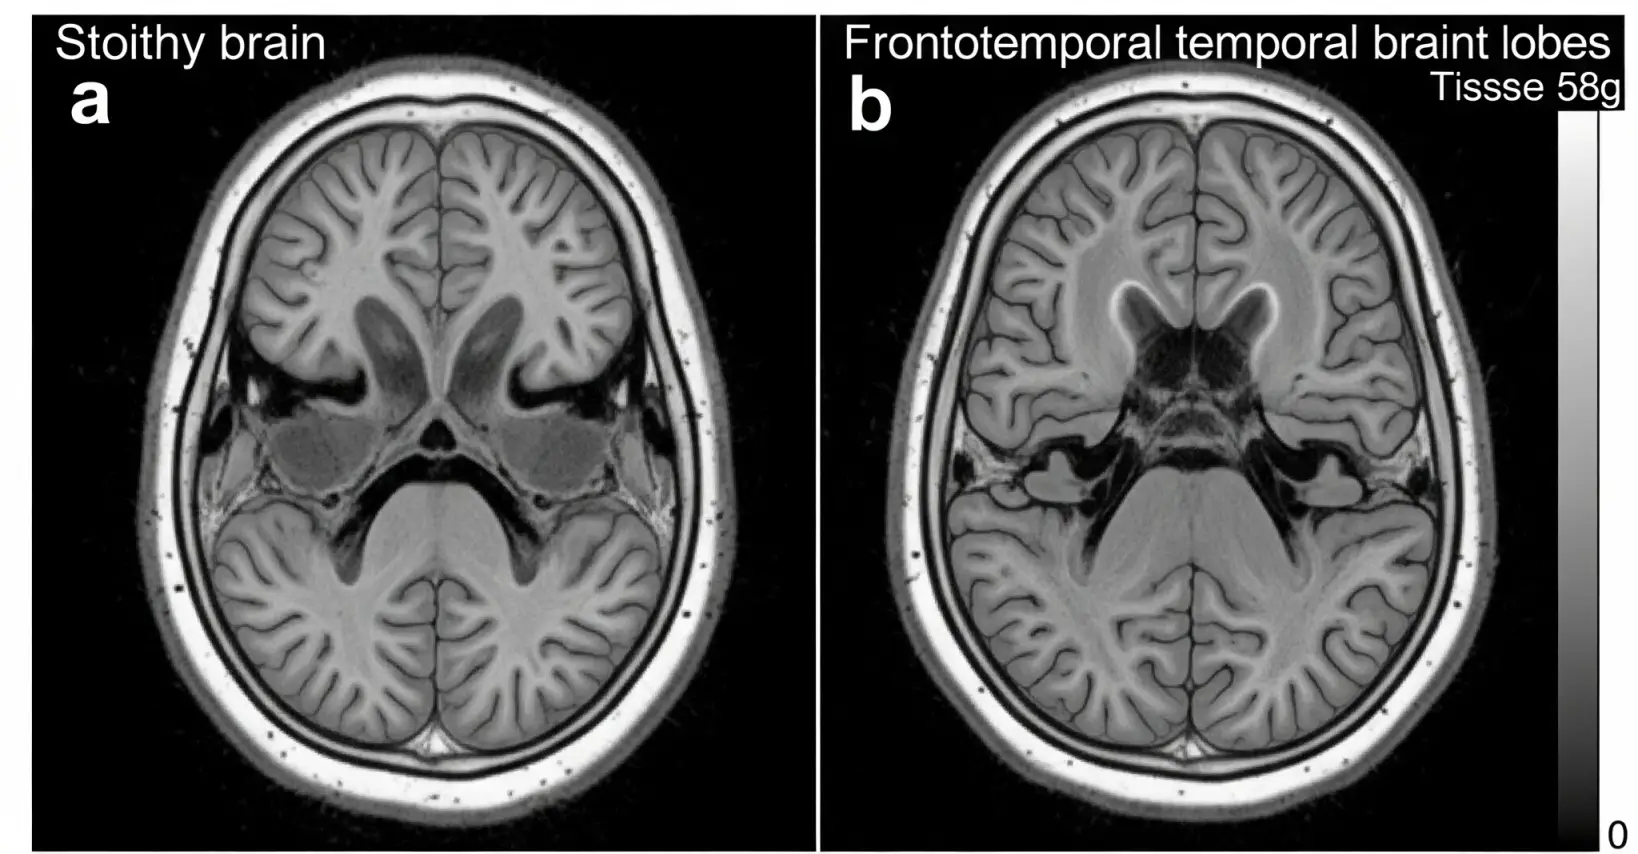

① 뇌 앞부분에 문제가 생기는 치매예요

전두엽과 측두엽은 감정, 언어, 판단력을 담당하는 뇌의 앞쪽 부분이에요.

이 부위에 신경세포가 죽거나 위축되면, 말이 어눌해지고 성격이 바뀌고, 감정 표현도 둔해지죠.